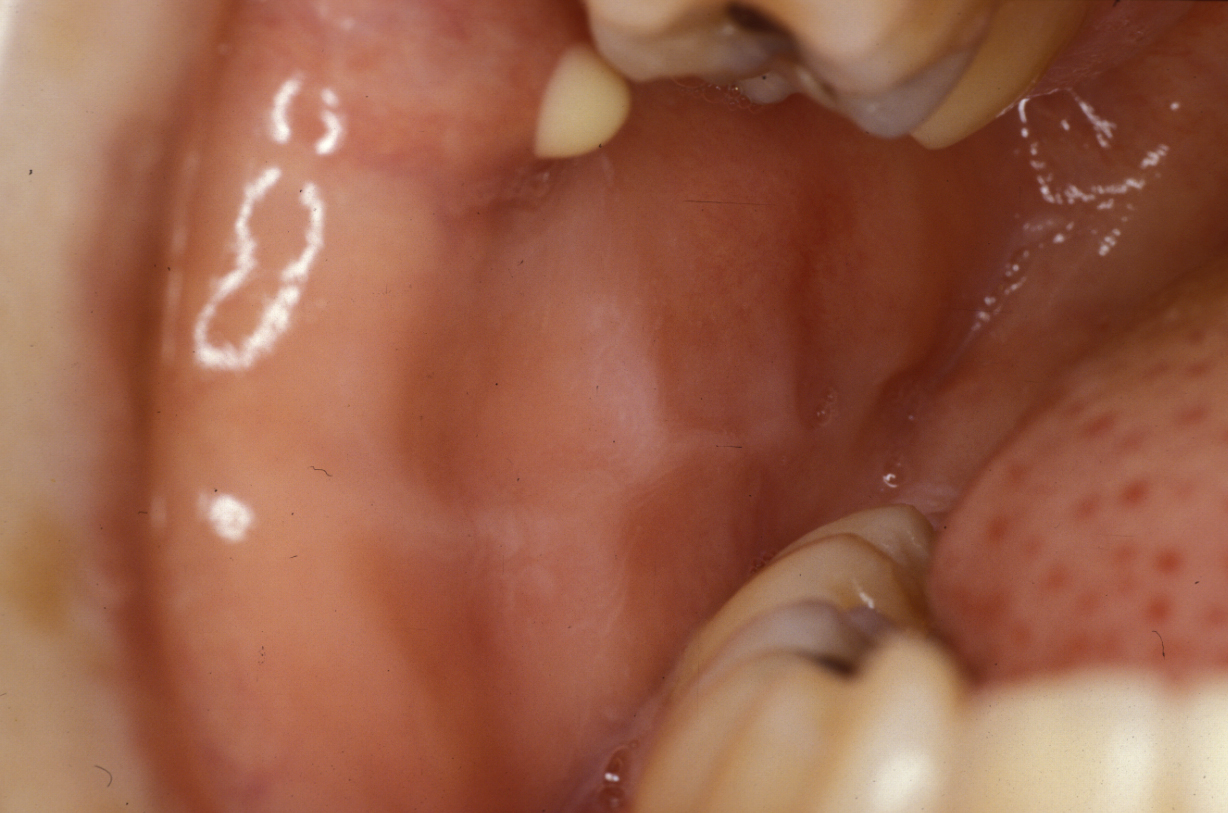

Necrotising sialometaplasia is a non-malignant condition of salivary gland tissue which clinically can appear to be a malignant tumour. It is a rare condition and occurs more commonly in men, usually in their 30s and 40s. The most common area is the palate and it presents as an ulcer. It has a short clinical course, with the ulcer appearing over a period of up to two weeks or so. This short history is a clue to diagnosis. Biopsy is mandatory to exclude carcinoma. Histopathologically the biopsy can be just as difficult to differentiate from cancer as the clinical appearance. The lesion heals by secondary intention (without intervention) in two to three months. More rapid healing can be obtained by excision with a small rim of normal mucosa and placement of a dressing plate with an obtundant (pain reducing) dressing.